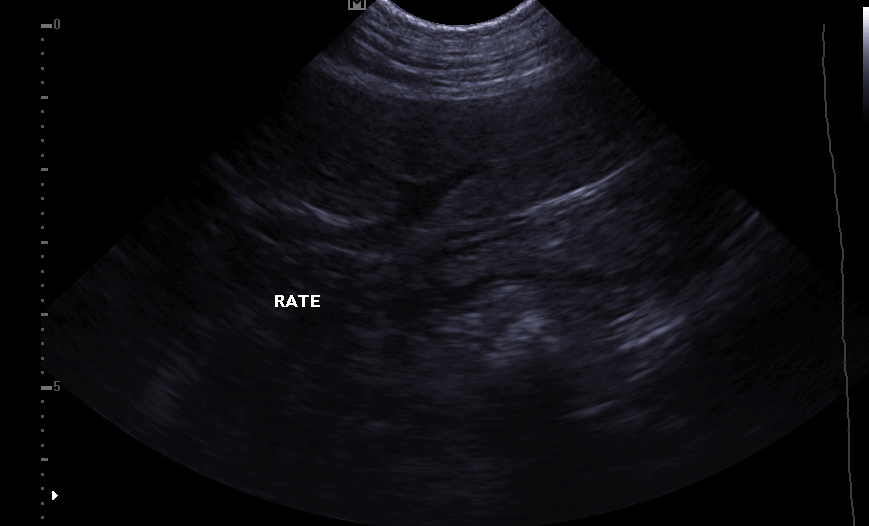

Es ermöglicht die Visualisierung der verschiedenen Teile des Herzens (Wände, Hohlräume, Klappen) und die Identifizierung von Anomalien, die eine korrekte Herzfunktion verhindern. Bei Herzinsuffizienz ermöglicht die Echokardiographie auch eine regelmäßige Überwachung der Herzmorphologie. Es ist dann einfacher, die Behandlung an Ort und Stelle neu einzustellen.